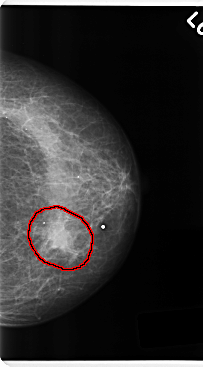

FILE: C_0216_1.LEFT_MLO.OVERLAY

TOTAL_ABNORMALITIES 1

ABNORMALITY 1

LESION_TYPE MASS SHAPE IRREGULAR MARGINS ILL_DEFINED

ASSESSMENT 4

SUBTLETY 5

PATHOLOGY MALIGNANT

TOTAL_OUTLINES 1

BOUNDARY

FILE: C_0216_1.LEFT_CC.OVERLAY

ASSESSMENT 5